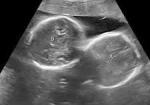

अल्ट्रासाउंड जांच में महिला के गर्भ में दो बच्चों की पुष्टि हुई थी -